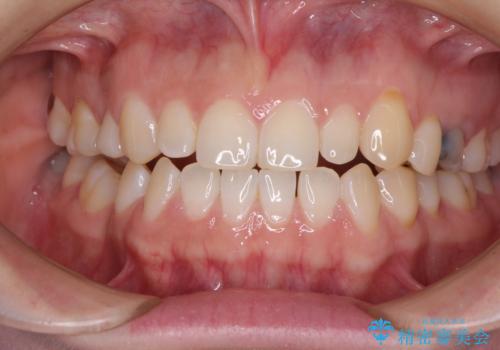

目立つ金属をすべてセラミックに 全顎的メタルフリー治療